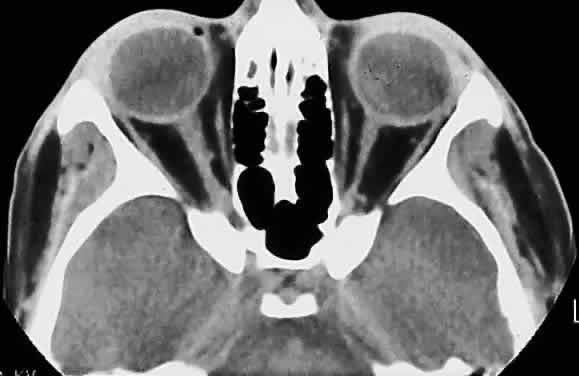

Hypoplasia of the optic nerve is also rare but is more common than aplasia (Figs. 13 and 14). It represents one of the most important developmental abnormalities of the eye and is increasingly recognized as a significant cause of visual deficit in children. Congenital nerve hypoplasia is a nonprogressive condition associated with a reduction in the number of retinal ganglion cells and axons. It may be either unilateral or more commonly bilateral and may involve the entire nerve or be segmental. Although a hypoplastic optic nerve is usually idiopathic, an increased incidence has been noted in the offspring of diabetic mothers and with the maternal use of phenytoin, quinine and, alcohol. Rare reports of an inherited disorder may be found in the literature. Although it may be an isolated abnormality, the hypoplasia is frequently associated with other anomalies—both ocular and nonocular. Additional ocular abnormalities include microphthalmos and congenital nonattachment of the retina. The most common nonocular abnormalities associated with congenital optic nerve hypoplasia include midline CNS structural defects, including septo-optic dysplasia of the septum and ectropia of the posterior pituitary, producing diabetes insipidus.

Fig. 14. Computed tomographic scan of head, showing hypoplastic left optic nerve.

In optic nerve hypoplasia, the optic disc appears gray and is about half its normal size but retinal vessels are present because the optic stalk is invaginated by mesoderm. The optic foramen is also small. Clinically, there may be strabismus, nystagmus, and decreased visual acuity. Severe cerebral abnormalities may be present but the hypoplastic nerve may be the sole abnormality.